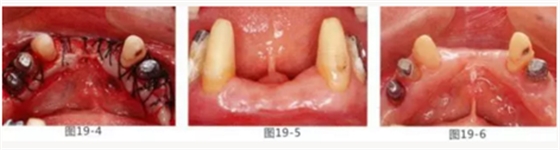

病例10

有少數(shù)牙體殘存的病例,需要進(jìn)行修復(fù)處理,將基牙和鉤牙部位的牙周袋去除以及對(duì)頰舌側(cè)進(jìn)行FGG(游離齦移植)來(lái)獲取附著齦的病例

圖19-1 右下3,4,左下3,4,5殘存牙頰側(cè)面照。唇頰側(cè)沒(méi)有附著齦。

圖19-2 同部位的舌側(cè)面照。雖然有1mm左右角化牙齦,但是進(jìn)行預(yù)測(cè)切開(kāi)的話,會(huì)使角化牙齦完全消失。

圖19-3 左下3,4,5部位進(jìn)行FGG(游離齦移植)去除牙周袋以及獲得附著齦。同時(shí)進(jìn)行骨外科處理。相反側(cè)也進(jìn)行同樣的處理。

圖19-4 將移植片固定于右下3,4左下3,4,5的舌側(cè)骨膜,并進(jìn)行牙周袋去除以及獲得附著齦。

圖19-5,6 術(shù)后1個(gè)月唇舌側(cè)的愈合狀態(tài)。唇舌側(cè)都獲得了足夠附著齦。